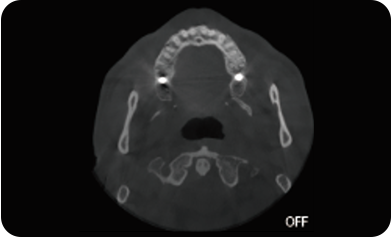

局部超清显示、 移动视野摄片

可根据临床需求任意调整成像区域大小实现局部超清三维显示

临床样片